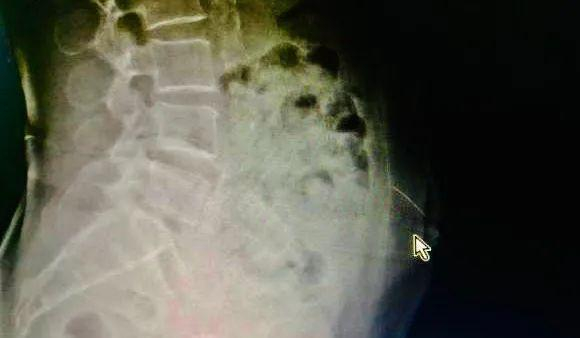

影像显示阿婆断针的位置

为了确认断针的位置并尽快把它取出来,潘裕国为阿婆做了CT定位和三维重建,发现针已从皮下组织扎到了腹直肌里,所幸未伤及内脏。